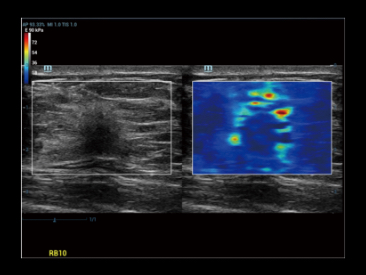

ElastografĂa de prĂłstata cualitativa por compresiĂłn y shear wave para dos mĂ©todos de biopsia diferentes.

ElastografĂa de prĂłstata: Carcinoma de prĂłstata

La nueva ElastografĂa Sound Touch (STE) permite tener una velocidad de cuadros mĂĄs alta en el campo, hasta 10 veces mĂĄs rĂĄpida que antes*, lo que brinda mĂĄs confianza en el diagnĂłstico clĂnico.

STE normal

STE de alta velocidad de cuadros